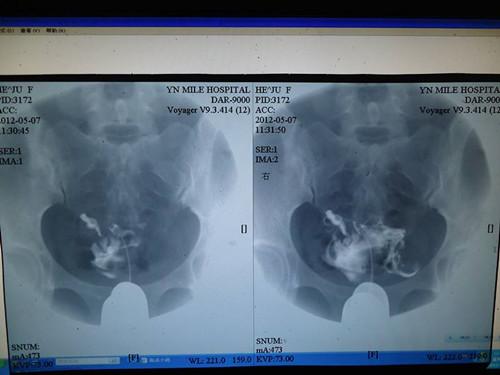

小梅月经周期规律,也无流产史,因此卵巢其实并无问题。之前看中医总是说是气血不足。 医院给小梅安排查输卵管照影,可能是之前在网上看了很多,检查的当天特别害怕。好在实际检查时,老公帮忙摆正心态,发现其实并不是网上说的那么恐怖。

然而最后出来的结果却是“双侧输卵管通而不畅,均有炎症粘连。”考虑到小梅已经30多了,自主怀孕已是不易,于是决心先行冻卵,以备将来。